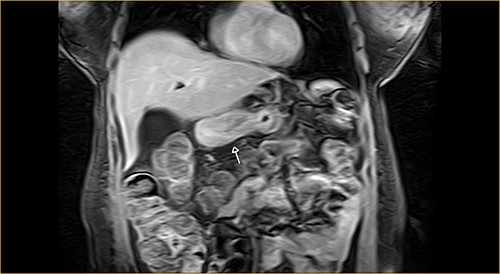

Laboratory examination showed anemia. An excluded stomach distention and parietal thickening of the pylorus and antrum were identified during abdominal computed tomography (CT) and magnetic resonance imaging (Figs 1–4). Thoracic CT was normal.

Transversal section on T2-weighted magnetic resonance showing excluded stomach distention with parietal thickening of the pylorus and antrum (arrow).